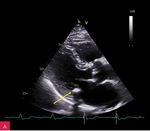

Rycina 1A, B. Zwapnienie w pierścieniu mitralnym (MAC) u podstawy tylnego płatka mitralnego w projekcji przymostkowej w osi długiej LAX (A) i w osi krótkiej SAX (B)

Zwapnienie pierścienia zastawki mitralnej (MAC – mitral annular calcification) stanowi następstwo przewlekłych zmian degeneracyjnych i jest dość często spotykane u osób w starszym wieku (ryc. 1). Serowate zwapnienie pierścienia mitralnego (CCMA – caseous calcification of the mitral annulus) to rzadki, często niedostatecznie rozpoznawany wariant MAC. CCMA stanowi ok. 0,6% wszystkich przypadków MAC, występuje rzadziej niż w 0,1% populacji ogólnej. Częściej dotyka starszych kobiet, szczególnie z nadciśnieniem tętniczym, przewlekłą chorobą nerek lub zaburzeniami gospodarki wapniowo-fosforanowej1,2. Zmiana zazwyczaj obejmuje tylny pierścień zastawki mitralnej i składa się z uwapnionej otoczki oraz wnętrza wypełnionego mieszaniną wapnia, kwasów tłuszczowych i cholesterolu, przypominającą konsystencją pastę do zębów3,4. CCMA może osiągać duże rozmiary, szerząc się w kierunku tylnego płatka mitralnego oraz mięśnia lewej komory w zakresie ściany dolno-bocznej i dolnej.